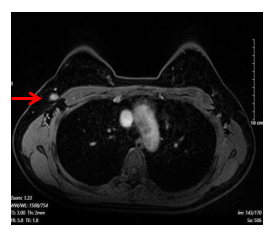

- Chụp cộng hưởng từ tuyến vú hai bên: (03/07/2024)

+ Vú Phải:

· Vị trí góc ¼ trên trong có khối kích thước 25x61mm, tăng tín hiệu trên STIR, hạn chế khuếch tán trên DWI/ADC, sau tiêm ngấm thuốc sớm, tăng dần, không thấy thải thuốc.

· Không thấy hình ảnh tụt núm vú, không thấy co kéo da

· Hạch hố nách bên phải,chặng I có vài hạch, có vỏ dày, kích thước lớn nhất 7x13mm

+ Vú trái: Hệ thống ống tuyến cân đối, không thấy khối, không tụt núm vú, không co kéo da

Hình 1. Hình ảnh chụp cộng hưởng từ tuyến vú: Hình ảnh khối u vú phải kích thước 25x61mm, sau tiêm ngấm thuốc sớm, tăng dần, không thấy thải thuốc (mũi tên màu đỏ)